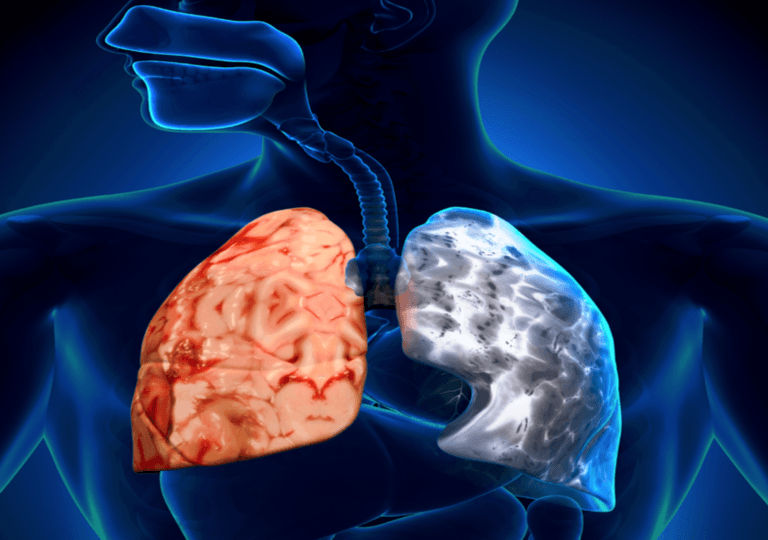

Η Χρόνια Αποφρακτική Πνευμονοπάθεια (ΧΑΠ) είναι μια προοδευτικά εξελισσόμενη πάθηση που οδηγεί σε εξασθένηση του αναπνευστικού συστήματος, με σοβαρές συνέπειες τόσο σε ιατρικό όσο και σε οικονομικό επίπεδο. Εκατομμύρια άνθρωποι σε όλο τον κόσμο πάσχουν από τη νόσο ενώ τα ποσοστά νοσηρότητας και θνητότητας είναι υψηλά. Η ελλιπής γνώση σχετικά με τους παράγοντες κινδύνου και τα συμπτώματα που σχετίζονται με την ασθένεια υποδεικνύει ότι η εν λόγω νόσος υποτιμάται και δεν διαγιγνώσκεται επαρκώς. Αυτά είναι συμπυκνωμένα τα βασικά στοιχεία για τη ΧΑΠ, η οποία είναι δυστυχώς μια νόσος που το κοινό υποτιμά και παραγνωρίζει, τουλάχιστον στην Ευρώπη όπως προκύπτει από έρευνα που δόθηκε στο φως της δημοσιότητας.

– Στους κύριους παράγοντες κινδύνου συγκαταλέγονται το κάπνισμα και η ατμοσφαιρική ρύπανση, με ποσοστό 80% και 54%, αντίστοιχα.